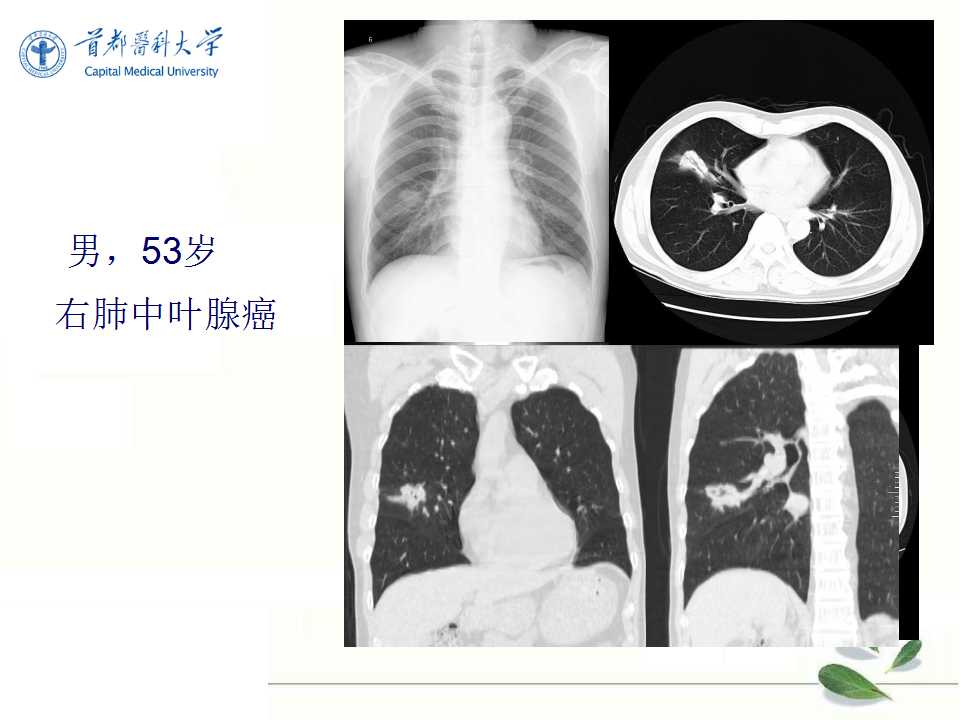

肺癌的影像学检查